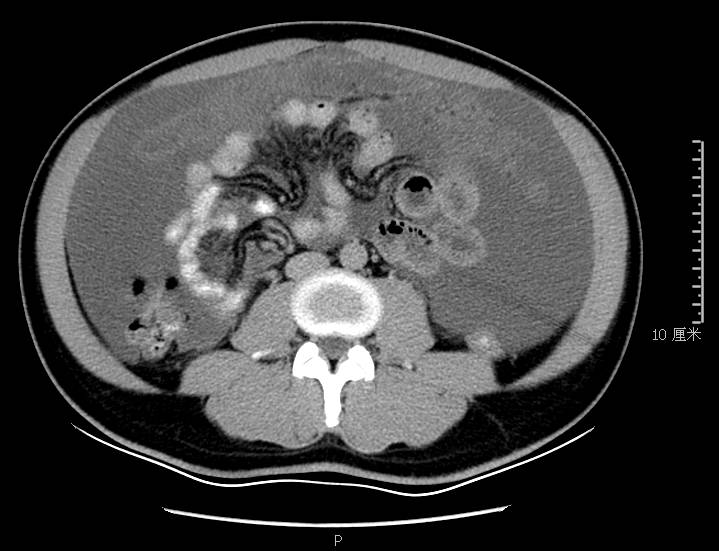

全腹CT:(1)结合病史考虑腹膜炎(见图2A),大量腹水;(2)右骼窝区管状样结构,考虑阑尾扩张(见图2B);(3)肝脏多发小囊肿(见图2C);(4)肝内胆管轻度扩张,建议隔期复查。

图2a大网膜成饼状(CT腹腔横断图象上出现肠曲被前面及两侧的肿瘤组织限制在中央

图2b扩张成管状阑尾

本例确诊后对B超及CT再次回顾发现:腹腔、盆腔可见不均质中强回声包块,部分呈囊实状,腹膜增厚,大网膜成饼状(如图2A)和肝周可见不均质中强回声弧形压迹、脾周可见不均质中强回声包饶,肝脏成扇贝样改变(如图2C),但在诊断报告中未提及。有学者发现mantle和scalloping(如图2A,2C)在PMP中具有代表性,且mantle较scalloping更为常见,若mantel征同时伴有大小不一的囊性改变,则更具诊断价值。

图2c肝脏成扇贝样改变(肝脏由于受肿瘤实质性或囊性组织压迫而其实质却未受侵犯,于是在一处或多处呈下凹状或扇形皱褶状(scalloping)

通过本病例分析认为此类患者,腹穿时若发现腹水不易抽出或抽出物为黏稠胶冻样,腹部B超提示液性暗区内有漂浮的团状回声有分隔,撞击腹部后可出现“礼花”样改变,肝脾包膜完整不光滑,有弧形压迹,全腹部CT示弥散占位,可见mantle和scallping征、大网膜成饼状且阑尾扩张应高度怀疑本病。